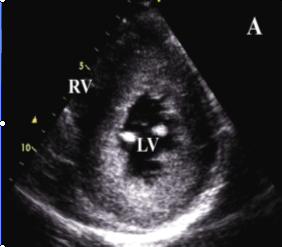

糖尿病性腎病Ⅴ期:腎功能衰竭期。糖尿病病人一旦出現持續性尿蛋白發展為臨床糖尿病腎病,由於腎小球基底膜廣泛增厚,腎小球毛細血管腔進行性狹窄和更多的腎小球荒廢,腎臟濾過功能進行性下降,導致腎功能衰竭,最後病人的GFR多<10mL/min,血肌酐和尿素氮增高,伴嚴重的高血壓、低蛋白血症和水腫。病人普遍有氮質血症引起的胃腸反應,如食慾減退、噁心嘔吐,並可繼發貧血和嚴重的高血鉀、代謝性酸中毒和低鈣搐搦,還可繼發尿毒症性神經病變和心肌病變。這些嚴重的合併症常是糖尿病腎病尿毒症病人致死的原因。

3.晚期並發心血管多種疾病如動脈硬化、心包炎、結腸炎、出血性疾病及神經系統病變。

(1) 長期血透:從20世紀60年代初期就已開始對晚期糖尿病腎病病人套用透析治療,近年來接受血透者有所增加。如1972年還不到0.5%,1981年上升到7.3%,根據1988年美國統計因糖尿病腎病腎功能衰竭接受血透者約為新血透病人的28%。但由於終末期糖尿病腎病除腎臟病變外,幾乎同時都合併有其他器官的血管合併症,特別是由於全身性小動脈硬化,血管壁僵硬,血透的血管通道難以建立,動靜脈瘺管在糖尿病人保留的時間明顯短於非糖尿病人。因此,糖尿病腎病病人血透的存活率,儘管過去10年有了改善,但仍低於非糖尿病人,據Matson與Kjellstrand對369例長期血透病人的隨訪分析,3年累積存活率為45%,5年25%,10年為9%,年齡在60歲以下的1型糖尿病腎病病人血透的存活率20世紀80年代較之60年代有了明顯的提高,1年存活率由60%上升為85%,3年存活率由30%上升為60%,5年存活率由12%上升到45%。但Jacobs等報導歐洲1098例第1年存活率為67%,第2年為49%。1型糖尿病血透病人的死亡率幾乎為非糖尿病人的2.5~3倍,死亡原因仍以心血管合併症為主占51%,其次為中止透析占24%,感染占14%,其他如電解質紊亂(高鉀或低鉀)、高滲性昏迷等約占11%。血透的預後與糖尿病類型有關,1型病人的存活時間明顯短於2型病人,但2型病人有心血管合併症者存活時間短;病人年齡>60歲者預後差,60歲以下則差別不大;至於是否合併有糖尿病視網膜病變對預後關係不大。